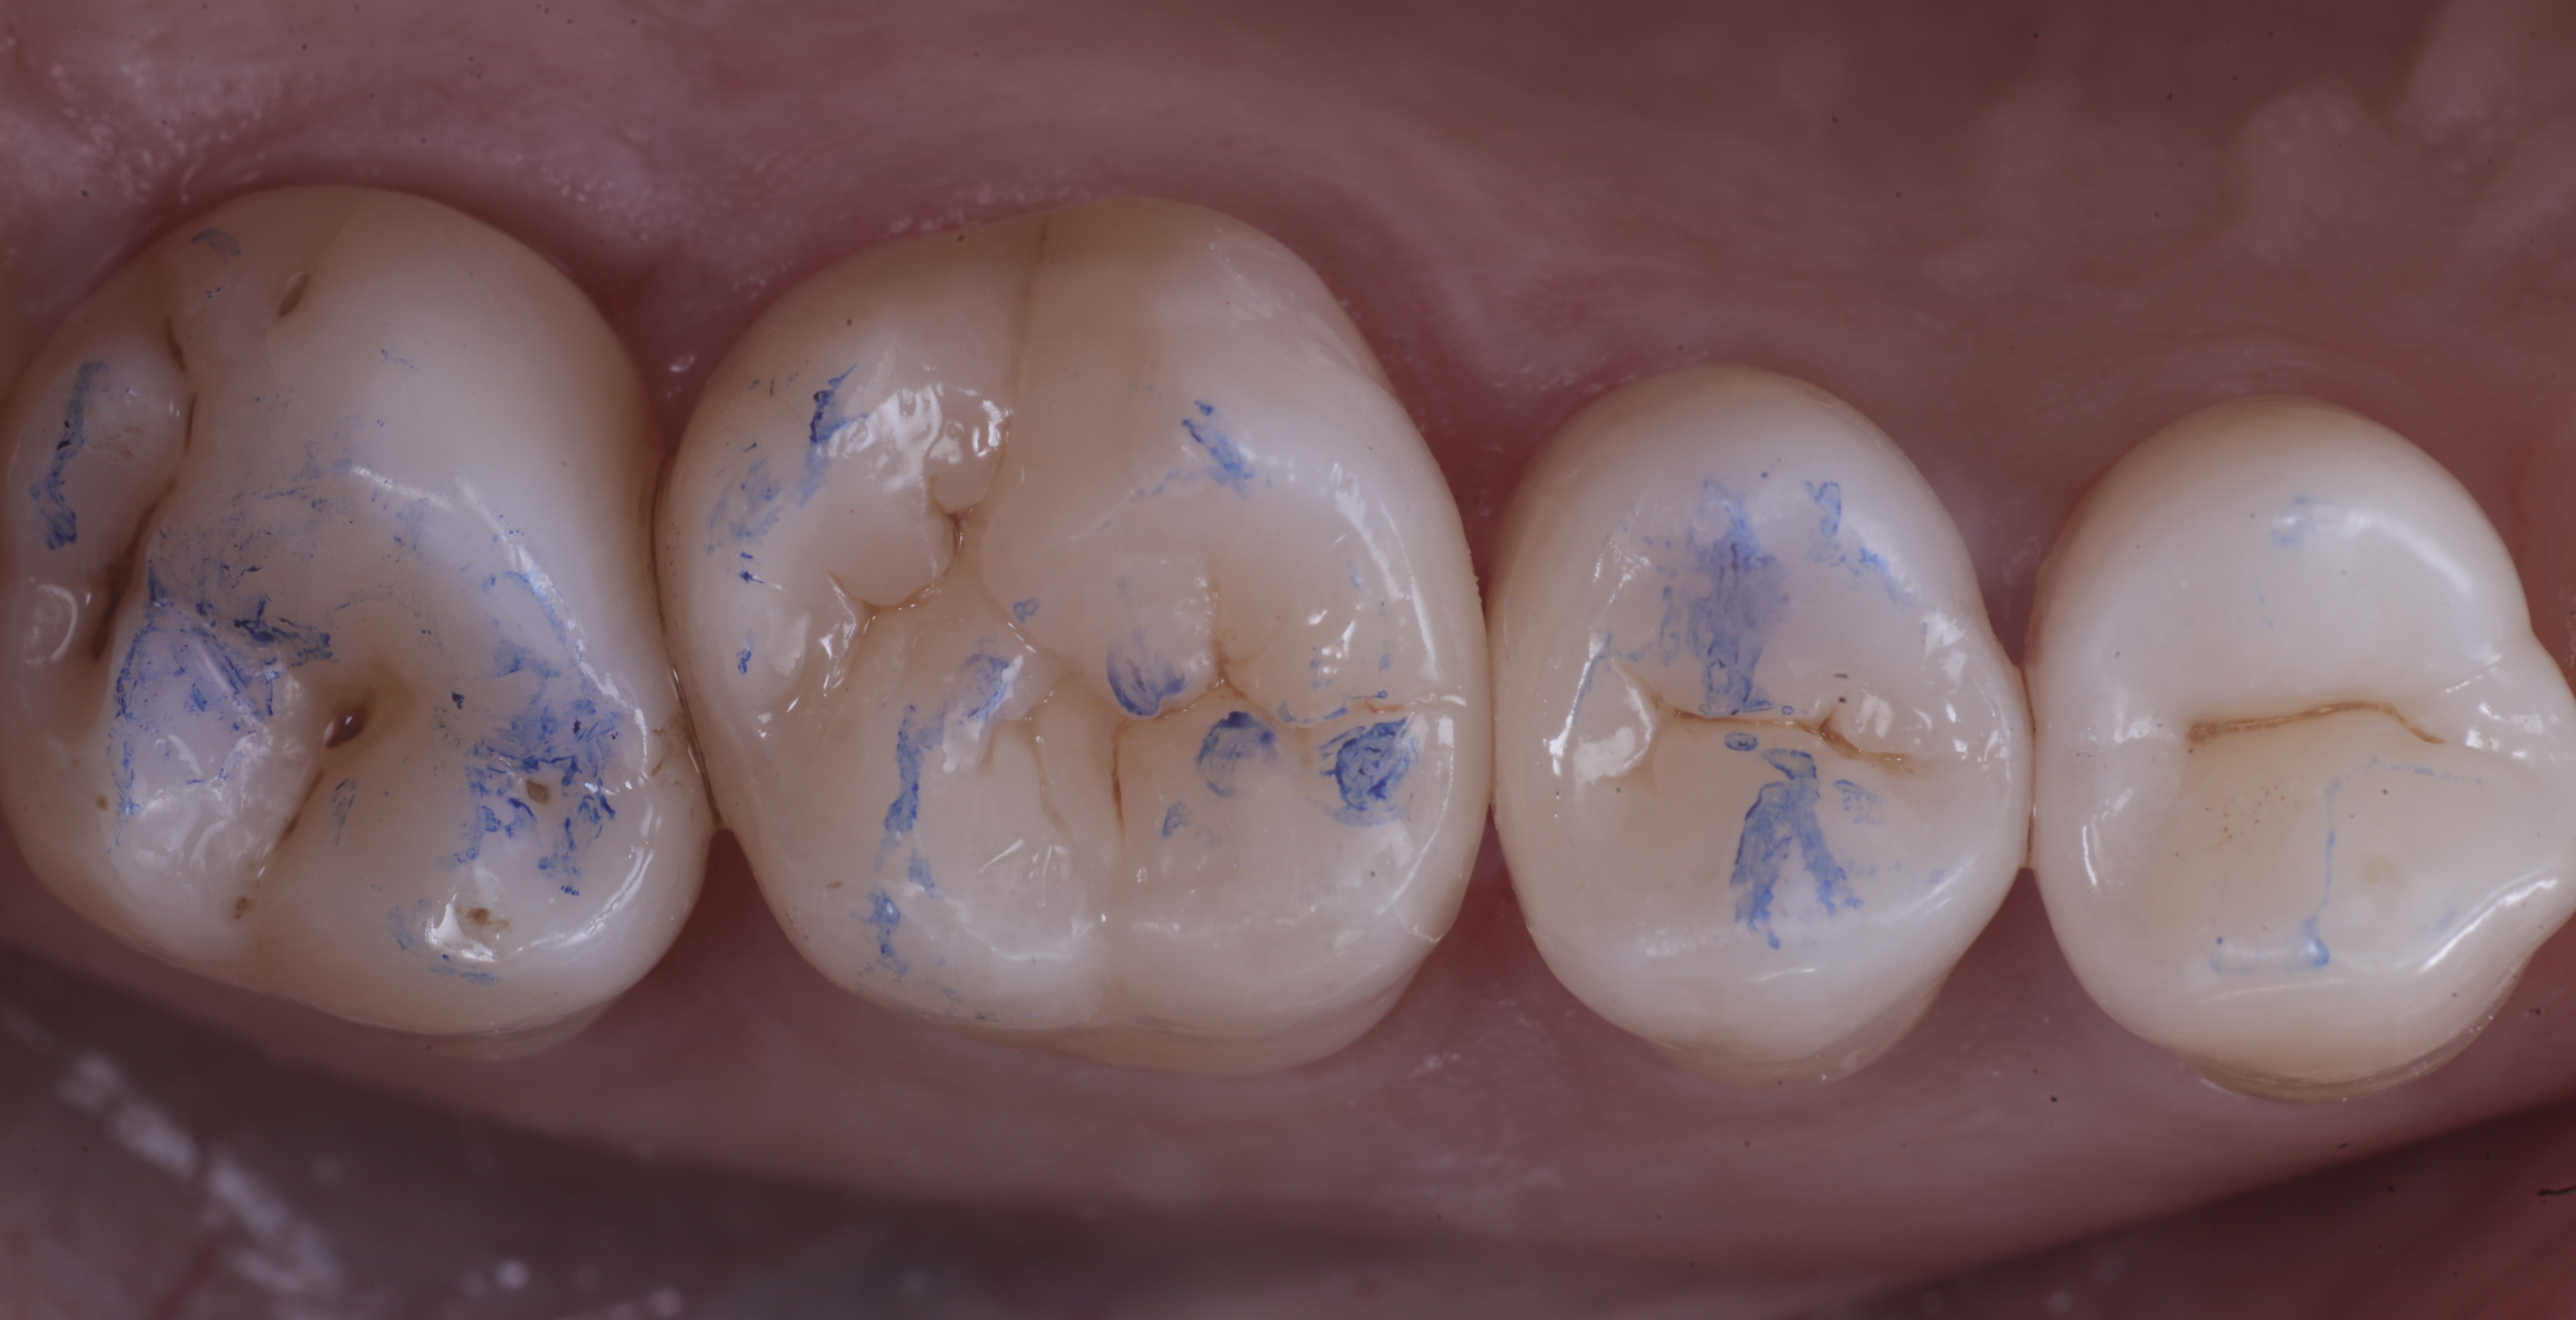

foto 11 Restauri ultimati sotto controllo occlusale